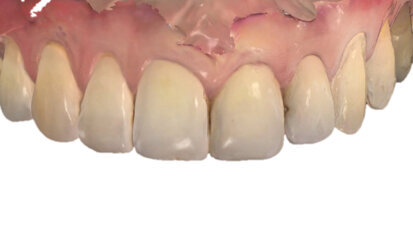

Bělení zubů a ortodoncie: třešnička na dortu

Bělení zubů je terapeutickou procedurou, která představuje poslední krok ortodontické léčby. Cíle ortodontické léčby jsou jak funkční – ...